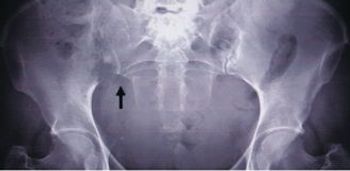

A 29-year-old African American woman came to our rheumatology clinic with right hip pain that had been getting worse for the past 3 months. She had been diagnosed with systemic lupus erythematosus (SLE) 2 years earlier. She reported excruciating right hip pain and mild pain in her left hip on weight bearing and, occasionally, at rest.

A 48-year-old woman presented to the orthopedic clinic with dull, persisted pain in the sacroiliac area that was impervious to NSAIDs. She denied knowledge of any injury or other possible explanation.